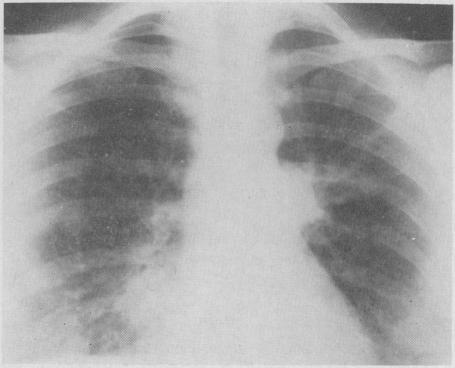

Non-chromaffin paraganglioma of the kidney with distant metastases.

Can Med Assoc J. 1968 Dec 7;99(22):1095-8.